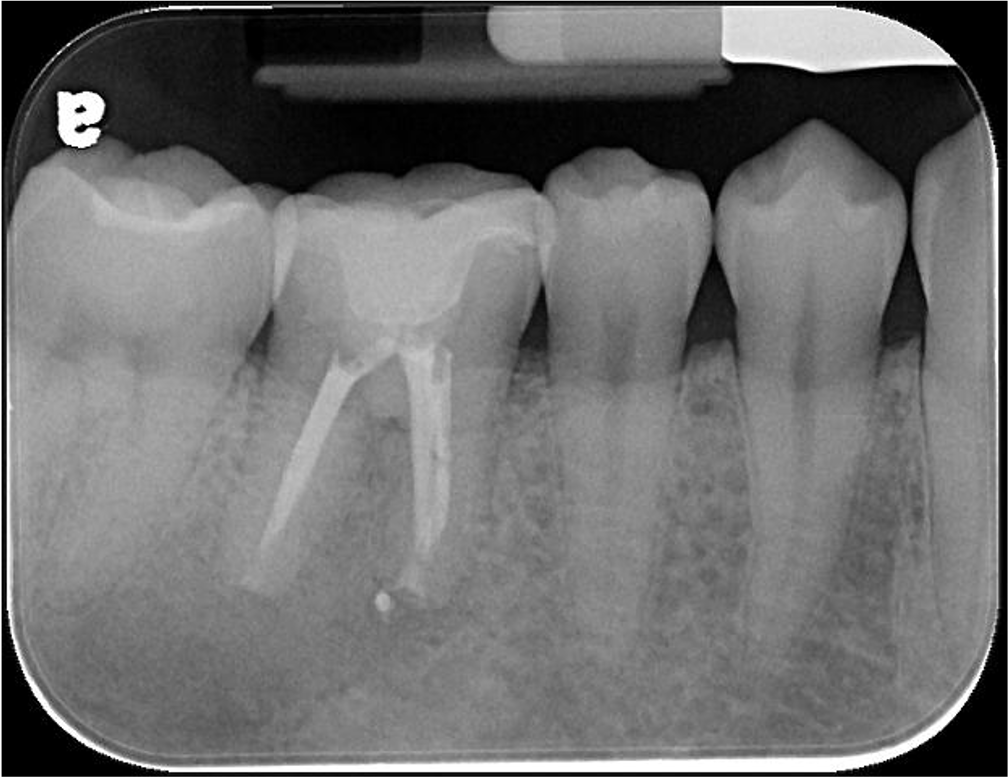

治療前,蛀牙與根尖破壞

先進行非手術顯微根管治療

牙齒拔出,刮除根尖病變

6個月後,根大病變癒合

根尖病變持續癒合

巨大的根尖病變,有時需要牙髓手術輔助,才能順利拯救牙齒,而現今陶瓷冠塊體修整牙齒較少,可有效保護牙齒結構。